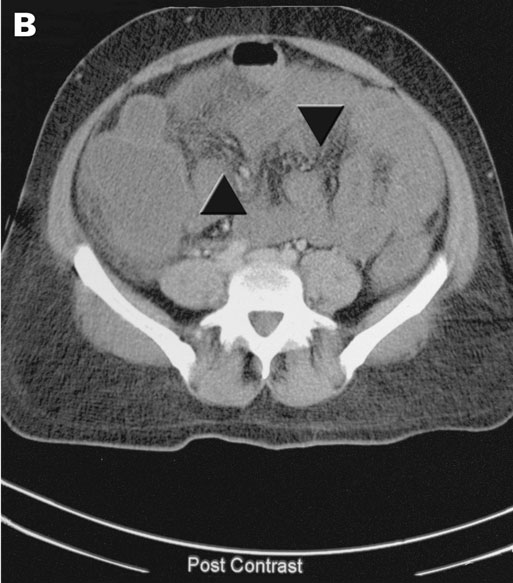

The next day, cerebral computed tomography (CT) scan showed changes in the basal ganglia and mild generalised cerebral swelling consistent with severe hypoxia (Box 2A). A CT scan of her abdomen showed generalised changes in the bowel wall and mesentery consistent with bowel necrosis (Box 2B). Surgical intervention was considered to offer little in view of the severe neurological damage and multiorgan failure. Following extensive discussion with family members, inotropic support was withdrawn and she died soon afterwards.